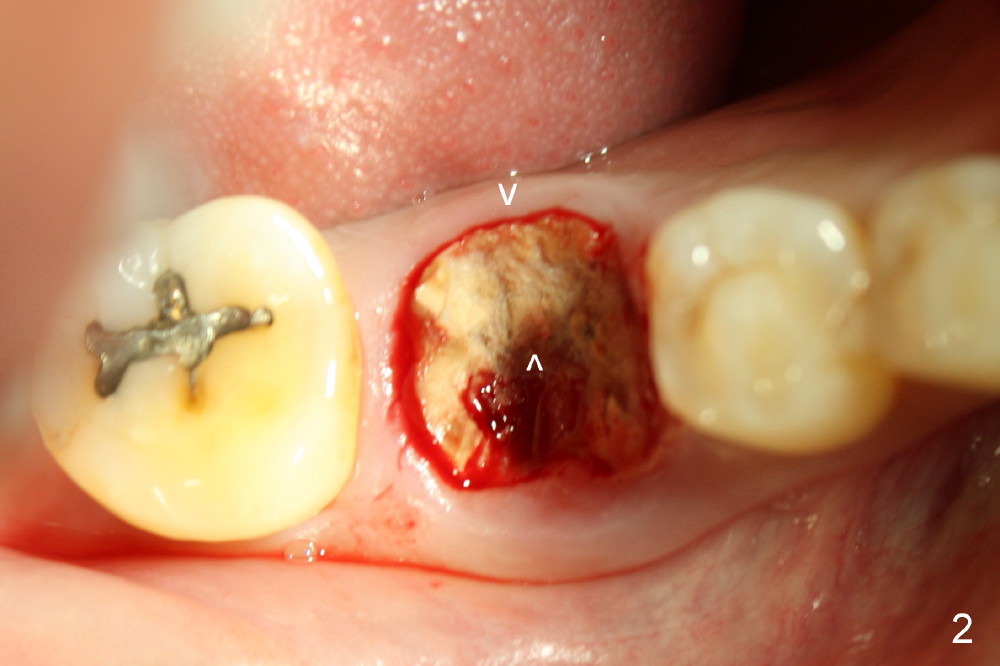

A sixty-year-old lady fractured the crown of the lower right first molar (Fig.1). The residual roots were sectioned (Fig.2 between arrowheads) and removed. The septum (Fig.3 *) is round on the top between mesial and distal sockets (1,2). Thin osteotomes (bone scalpel, bone blade; Fig.4: T) were used to section the septum mesiodistally. Fig.5 shows the sectioned septum, which makes it easy to insert round tapered osteotomes (Fig.5 inset green; Fig.6 R) without slipping either into the mesial or distal socket.